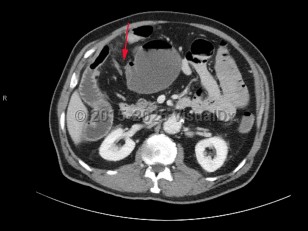

A small bowel obstruction (SBO) occurs when intraluminal bowel contents fail to pass through the small intestine. Impaired passage of bowel contents results in dilation of the proximal bowel, with fluid accumulation, gas production, increased intraluminal pressure, and bacterial overgrowth. This results in abdominal distension and pain, nausea, and vomiting, with risk of bowel ischemia and perforation.

- Ingestion of multiple magnets

SBOs can be classified as partial or complete. Partial SBOs permit some passage of bowel contents past the obstruction site, while complete SBOs are associated with the inability to pass any gas or fluid past the obstruction. Partial SBOs can further be stratified into high-grade or low-grade, depending on the severity of obstruction, with low-grade SBOs presenting with less severe symptoms. A simple SBO is characterized by a single point of obstruction. A closed-loop obstruction is characterized by occlusion of the bowel at 2 points and has the highest risk of ischemia due to occlusion of the blood supply.